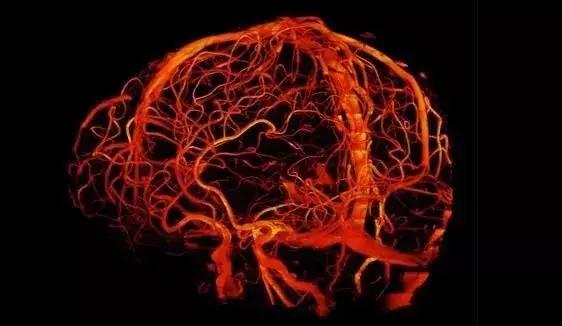

超高场(磁场强度)成像仪的吸引力是显而易见的,然而磁场越强,其信噪比越高,这意味着对物体的成像分辨率更高或成像速度更快。在3T时MRI成像仪能够解析1毫米大小的大脑结构,而在一台7T强度的成像仪下该分辨率就能达到0.5毫米,这就足以识别人类大脑皮层内部的功能单元,或许还能够观察到人类大脑中神经元连接之间的信息流,而具有更高场强度的成像仪预期的分辨率至少是7T设备的两倍以上。

研究者Ravi Menon表示,成像仪常常能为我们提供一些细节,而这些细节以前只能通过强大的显微镜成像技术在切片的尸检样本中观察到,而高强度的成像仪或许能为我们研究人类完整的大脑提供一扇强有力的窗户。

较好的分辨率也是喜忧参半的,因为其会使得成像仪对轻微的运动变得高度敏感,而一些由呼吸或心跳引起的机体重复运动或许也是可以被模拟或移除的。研究者Menon说道,最大的挑战就是7T甚至更高,这种强度目前在较低分辨率的成像仪中并不存在。如今7T强度的成像仪能通过揭示小于1毫米的结构来为研究人员开启研究人类活体大脑的新视野。

在被揭示的结构中有6层大脑皮层,3毫米厚得到大脑外层区域主要负责人类高水平的认知能力,而且每一层都非常特殊,一种负责处理来自大脑其它区域的信息输入,一些则进行信息处理并将处理结果传递到大脑的其它部分中。

如今成像仪的强度跨越到7T能够让研究人员测定不同大脑皮层的相对活性,进而就能阐明大脑信息的传递机制,这或许就是3T或1.5T成像仪时代的巨大进步,正常情况下我们提及A和B相连接时,我们只知道其具有相关性,但却并不知道信息之间是如何流动的。

一些研究小组已经利用这种能力来测定人们在进行语言和行为测试时的机体活动,而且研究结果揭示了不同层次的活动如何改变大脑皮层不同区域对机体自身体验的处理[2];研究者Menon说道,不仅仅是大脑的A区域会负责视觉,其还受到了注意力、情绪和记忆力的调节,而诸如此类问题却很难在动物模型中进行回答,如今在人类机体中使用7T磁通量的成像仪,研究人员将会得到以前无法看到的一幅人类记忆的图像。

研究人员希望能对人类大脑的柱状组织进行深入研究,大脑的皮层柱结构被认为会发挥计算的能力,同时还会对特殊的刺激优先产生反应,比如物体的方位等;虽然仅有500微米大小,但皮层柱垂直于大脑皮质层,且能通过中间层来进行互相通信,如果成像仪能在柱状水平下测定大脑的活性,那么科学家们就能够对单个神经元的计算得出结论,这将会让人非常激动,因为磁共振成像仪的一个局限性就是其无法直接测定大脑的神经活性。

7T磁通量的成像仪能够更好地帮助测定大脑的连接性,研究人员旨在完全绘制出大脑神经元间的连接,如今他们利用3T和7T的成像仪对184名个体进行了扫描,相比3T而言,在7T磁通量下,研究者能够检测到神经元之间的沟通以及较多的神经网络,这或许对于未来研究人员准确预测人类疾病至关重要。